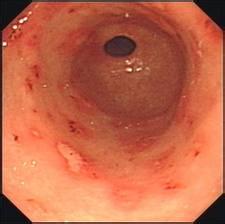

你好,这个三七粉对胃病的治疗作用不大。建议还是积极胃镜检查。需要看慢性胃炎还是消化性溃疡。需要服用药物胃康灵胶囊或者三九胃泰胶囊治疗。另外不能吃辛辣刺激性食物。